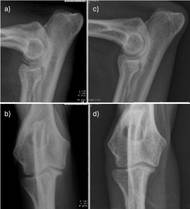

Žáková M. Ischemické príhody spôsobujúce spinálne a neuromuskulárne problémy u psov. ČasťII: Ischemická neuromyopatia- popis prípadu. Veterinární klinika 2026;23:13-19. SOUHRNV tomto článku je prezentovaný prípad psa s perakútnym nástupom paraplégie v dôsledku aortálnej tromboembólie. Jedná sa o veľmi netypický priebeh tohto ochorenia u psov. Prevedenou diagnostikou bol identifikovaný tromboembolus v…